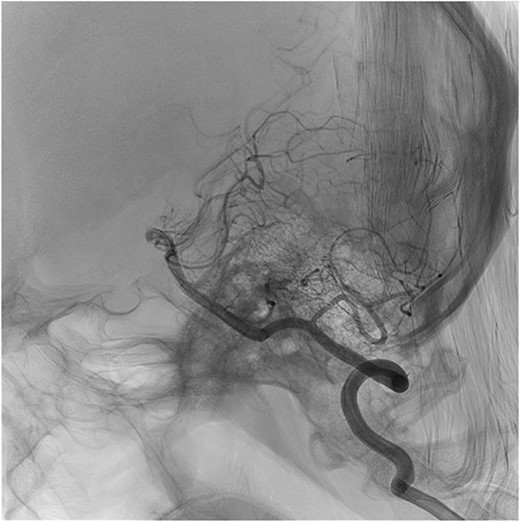

During post-operative day 1, the patient experienced paresthesias in upper and lower extremities, motor weakness (0/5 in bilateral lower extremities and 2/5 in the left upper extremity), loss of bladder sensation and urinary retention requiring a foley catheter insertion. Neurology team assessed the patient, diagnosing an anterior spinal cord syndrome. Chin stitches were removed and neck flexion was reduced to 30°, and an emergent cervico-thoracic spine magnetic resonance was performed to evaluate vascular damage. T2 and STIR sequences showed cervical kyphosis and two hyperintense lesions in the ventral spinal cord at the level of C4–C5, and the gray matter of C6–C7 (Fig. 1). Posteriorly, a brain angiogram was performed to rule out arterial occlusions with no suggestive findings of artery damage (Fig. 2).

Sagittal cut of MRI T2 sequence with evidence of medullary ischemic lesion in C5, and C6–C7 (arrows).

Sagittal cut of cerebral panangiography showing permeability of vertebral arteries.

Compromise of anterior spinal artery results in upper motor neuron signs, loss of pain and temperature sensation, bladder and bowel dysfunction [5]. This patient had a kyphotic cervical spine because of previous head trauma. Given the large tracheal resection, post-operative care demands neck hyperflexion to prevent anastomotic dehiscence. The probable mechanism for cervical spinal cord ischemic injury was related to the neck position. After neck position was corrected, the patient’s condition started improving. Additionally, the brain angiogram ruled out the presence of occlusive vascular injuries, indicating that posture change probably restored arterial flow. It is worth mentioning that, in the absence of a brain angiogram with neck in hyperflexion, this conclusion is based on indirect evidence.